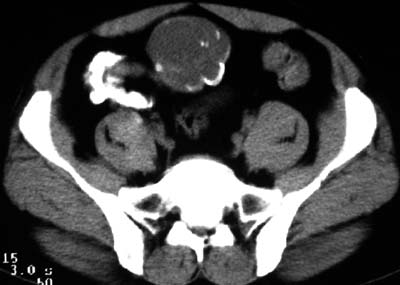

一、女,43岁,下腹部不适,子宫增大并可触及一硬物,活动度大。

典型的盆腔畸胎瘤。

病例1、盆腔畸胎瘤。病例2、盆腔占位压迫膀胱?还是膀胱占位?强化吧!

典型的盆腔畸胎瘤伴子宫肌瘤。

例1:畸胎瘤;

病理1.盆腔畸胎瘤和并子宫肌瘤

病例1、盆腔畸胎瘤,子宫体积增大,子宫肌瘤?病例2,囊腺瘤?

病例1,盆腔畸胎瘤并子宫肌瘤;病例2,囊性肿块,周围有壳状钙化,膀胱受压改变,考虑:脐尿管囊肿并感染,畸胎瘤?

考虑盆腔内畸胎瘤,子宫体积增大,建议增强扫描除外子宫病变